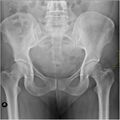

В строении таза у взрослого человека чётко прослеживаются половые особенности и отличия. Особенности в анатомии женского таза проявляются в первую очередь его большим размером, большим объёмом и увеличенной нижней апертурой. Данные анатомические отличия связаны с функцией — таз у женщин является вместилищем развивающегося плода, который впоследствии во время родов проходит через нижнюю апертуру таза. Таким образом таз у женщины шире и ниже, а все его размеры больше, чем у мужчины. Помимо этого кости женского таза тоньше, чем у мужского. Крестец у мужчин вогнутый и более узкий, а его мыс выражено выдаётся вперед. У женщин крестец, наоборот уплощён и более широкий, мыс выражен меньше и не так выдаётся вперёд, благодаря чему верхняя апертура женского таза является более округлой, чем у мужского. Подлобковый угол, под которым происходит соединение нижних ветвей лобковых костей, у мужчин является острым, а у женщин он приближается к прямому или даже тупому углу, его вершина является более закругленной, а ограничивающие его нижние ветви лобковых костей образуют лобковую дугу (аrcus pubis). Лобковый симфиз также характеризуется наиболее выраженными половыми особенностями строения. У женщин он короче по высоте, межлобковый диск более толстый, чем у мужчин. Небольшие движения у женщин в лобковом симфизе возможны во время процесса родовой деятельности, в то время как у мужчин движения в лобковом симфизе отсутствуют.

| Признак | Мужчины | Женщины |

|---|---|---|

| Общий вид таза | Узкий и высокий | Широкий и короткий |

| Расположение крыльев подвздошной кости | В большей степени горизонтальное | Более горизонтальное |

| Крестец | Узкий и длинный | Короткий и широкий |

| Подлобковый угол | 70-75° | 90-100° |

| Угол наклона таза | 50-55° | 55-75° |

| Форма полости малого таза | Конусообразная | Цилиндрическая |

| Форма верхней апертуры, или входа в малый таз | «Карточное сердце» вследствие большого стояния вперед мыса | Округлая |

| Лобковый симфиз | Высота около 5,5 см, уже, полости может не быть | Высота около 4,5 см, толще, мягче, во время беременности прорастает сосудами, разрыхляется |